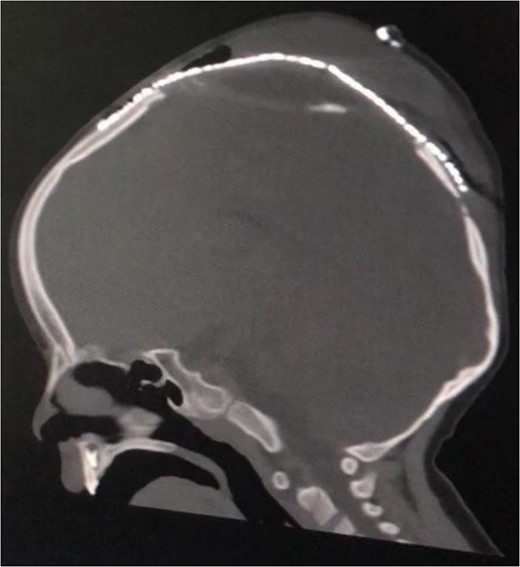

Postoperative sagittal brain CT demonstrating that the brain was inside the cranium and covered by the cranial mesh, preventing further bulging.